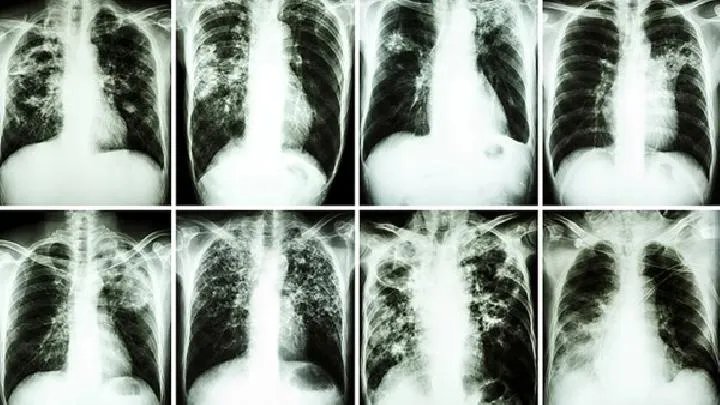

恶性肿瘤

恶性肿瘤分泌不成熟,生长迅速,渗透破坏器官的结构和功能,并可转移,对身体有严重影响。恶性肿瘤除了引起类似于上述良性肿瘤的局部压迫和阻塞症状外,更容易引起溃疡、出血,甚至穿孔,导致腹膜炎,后果更严重。有时肿瘤产品或合并感染会导致发烧。肿瘤浸润和压迫局部神经也会引起顽固性疼痛和其他症状。晚期恶性肿瘤患者,常发生恶性疾病质量(cachexia),它会导致病人的死亡。

近年来,一些非内分泌腺肿瘤可以产生和分泌激素或激素物质,如促肾上腺皮质激素(ACTH)、甲状旁腺素(PTH)、胰岛素,抗利尿激素(ADH)、绒毛膜促性腺激素(HCG)、促甲状腺激素(TSH)、生长激素(GH)、降钙素(calcitonin)等十余种,可引起内分泌紊乱的临床症状。此类肿瘤称为异位内分泌肿瘤,其所引起的临床症状称为异位内分泌综合征。此类肿瘤大多为恶性肿瘤,其中以癌为多,如肺癌、胃癌、肝癌、胰腺癌、结肠癌等;也可见于肉瘤,如纤维肉瘤,平滑肌肉瘤、横纹肌肉瘤和未分化肉瘤等。许多分泌异位激素的恶性肿瘤都有产生两种以上激素的特点。关于异位激素产生的机制于今尚无一致的解释,可能与瘤细胞内基因异常表达有关。